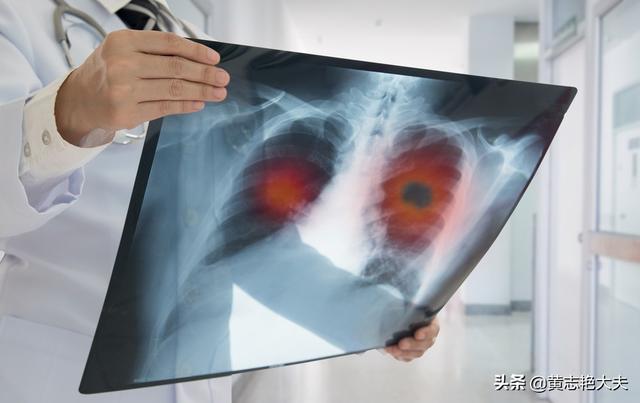

La plupart des cancers du poumon avancés forment des métastases dans le foie, le cerveau et les os et peuvent entraîner la défaillance d'un organe.

(3) Métastases tumorales

À un stade avancé, le cancer du poumon peut présenter de multiples métastases dans divers organes du corps. Le cancer du poumon métastase souvent dans le cerveau, le foie et le système vertébral squelettique, et les métastases cérébrales peuvent provoquer une hypertension intracrânienne. L'espace étant limité dans le cerveau, la propagation des cellules cancéreuses peut entraîner une hernie cérébrale et une hypertension intracrânienne, qui mettent en danger la vie du patient. Les métastases vertébrales peuvent entraîner des fractures pathologiques, une compression des nerfs, conduisant à la paralysie et même à la mort. Des métastases hépatiques multiples, qui peuvent entraîner un dysfonctionnement du foie et une insuffisance hépatique.

4. métastases tumorales, défaillance de plusieurs organes :Des métastases à différents organes peuvent se produire à un stade avancé du cancer du poumon, causant de grandes souffrances aux patients. Les patients atteints de cancer du poumon peuvent former des métastases dans des organes tels que la plèvre, le cerveau, les glandes surrénales, le foie, les os, le péricarde et ainsi de suite, provoquant une défaillance de plusieurs organes, qui peut entraîner la mort du patient.